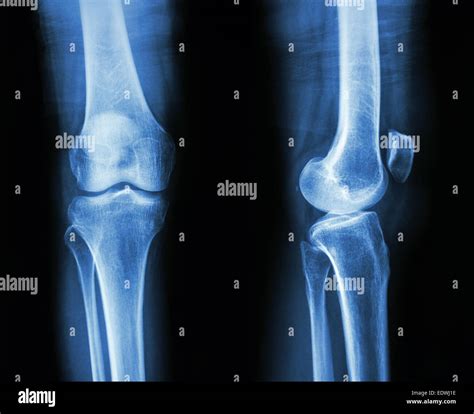

Interpreting Healthy Knee X-rays

Interpreting knee X-rays requires a trained eye. Here are some key features that radiologists look for in Healthy Knee X-rays:

• Bone Structure: The bones of the knee, including the femur, tibia, and patella, should appear smooth and intact without any fractures or deformities.

• Joint Space: The space between the bones should be uniform and not narrowed, which can indicate wear and tear or arthritis.

• Soft Tissue: While X-rays primarily show bone, the soft tissue around the knee should appear normal without any signs of swelling or inflammation.

• Alignment: The knee joint should be properly aligned, with no signs of dislocation or misalignment.

Common Findings in Knee X-rays

Knee X-rays can reveal a variety of conditions. Some of the most common findings include:

• Fractures: Breaks in the bone, which can range from small cracks to complete breaks.

• Arthritis: Degenerative changes in the joint, such as narrowing of the joint space and bone spurs.

• Dislocations: Misalignment of the knee joint, often due to trauma.

• Bone Spurs: Extra bone growths that can cause pain and limit mobility.